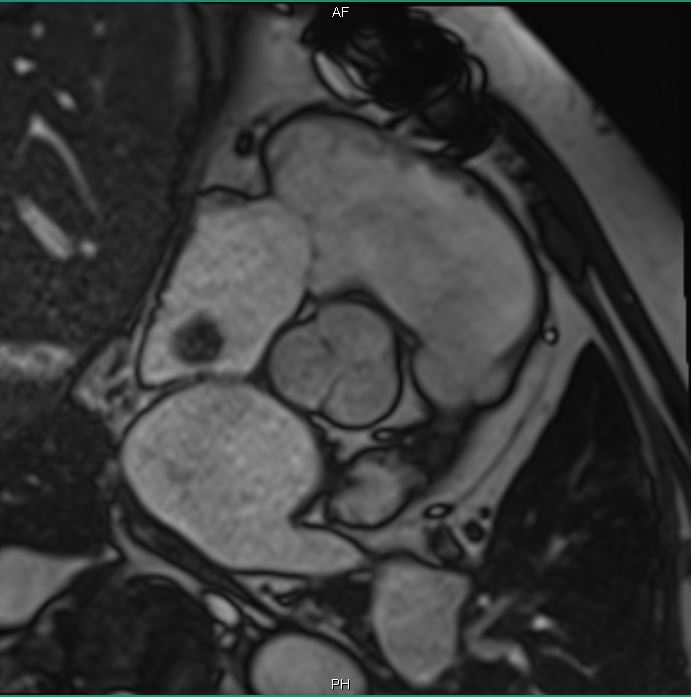

Cardiac MRI was performed on January 3, 2018, which revealed a large 2.5 × 2.9-cm lobular, fairly sessile mass in the right atrium. Without evidence of tissue destruction to suggest a malignant process, the lesion was suggestive of either myxoma or hematoma due to marked contrast uptake (which is seen less often with myxomas) (Figure 1).

Figures 1A-G. Cardiac MRI findings of a large, lobular, fairly sessile mass in the right atrium, measuring 2.5 x 2.9 cm, suggestive of either myxoma or hemangioma.